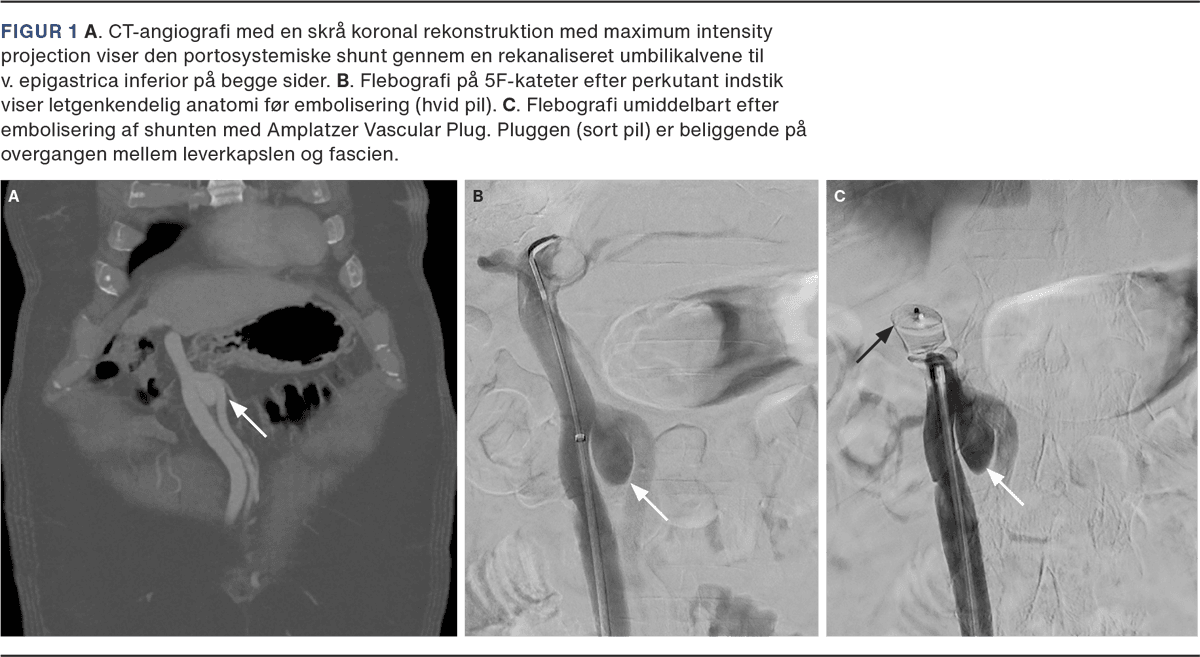

CT’en af leveren viste cirrose og en stor shunt mellem v. umbilicalis og v. femoralis (Figur 1 A). Diagnosen HE på baggrund af en portosystemisk shunt hos en patient med cirrose blev stillet. Patienten startede behandling med lactulose og rifaximin og blev på grund af manglende bedring af tilstanden henvist til Rigshospitalet med henblik på lukning af shunt. Der blev efterfølgende lavet perkutan embolisering af den portosystemiske shunt ved interventionsradiolog (Figur 1 B og Figur 1 C).

Spontane portosystemiske shunts ses hos op mod 60% af patienter med cirrose og øger risikoen for HE betragteligt ved at reducere den hepatiske ammoniumclearance. Hyppigst ses portosystemiske shunts via v. coronaria til øsofagus og splenorenale shunts, som løber fra v. lienalis til venstre nyrevene, som løber via ventriklen og giver fundusvaricer [4]. Den i sygehistorien observerede shunt mellem en rekanaliseret v. umbilicus via v. epigastrica inferior til v. femoralis er kun beskrevet én gang i litteraturen før, men ses formentlig hyppigere [5].